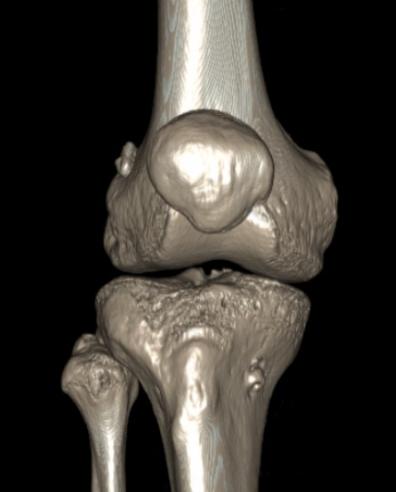

髌骨的活动是有轨迹的,正常情况下,它都待在一个类似于轨道的凹槽里,叫做股骨滑车。同时,依靠髌骨上下左右相连肌腱及韧带组织,将髌骨平衡在居中的位置上。

髌骨外偏

部分髌骨发育异常的患者,可以从外观看到一些端倪:髌骨有偏向外侧;有膝外翻的症状,膝盖靠拢脚踝靠不拢。